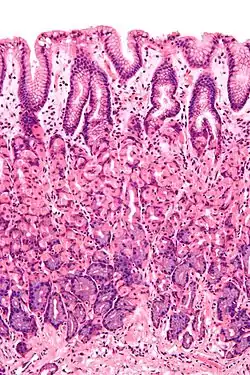

Secțiune histologică indicând mucoasa gastrică

- Mucoasa gastrică